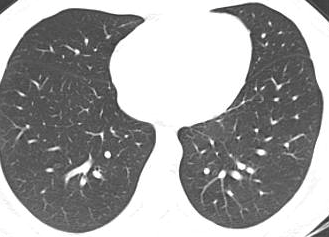

COVID19-CT dataset [51]: The dataset consists of a total of 746 CT images. There are 349 CT images of patients with COVID-19 and 397 CT images showing Non-COVID-19, but other pulmonary diseases. The positive CT images were collected from preprints about COVID-19 on medRxiv and bioRxiv, and they feature various manifestations of COVID-19. Since the CT images were taken from different sources, they have varying sizes between and . Figure 8 shows example CT images from the COVID19-CT dataset.

On the COVID19-CT dataset, the overall performance with respect to all evaluation metrics is inferior to that on the SARS-CoV-2 dataset. This can be attributed to the cross-source heterogeneity of the CT images in the dataset. The Non-COVID-19 CT images were taken from different sources and show diverse findings which pose difficulty to distinguish between COVID-19 and other findings associated with lung diseases due to the potential overlap of visual manifestations (see Figure 8). Another reason is that, the CT images in the COVID19-CT dataset show strong variations in contrast, variable spatial resolution and other visual characteristics, which could affect the model’s ability to extract more discriminative and generalizable features.